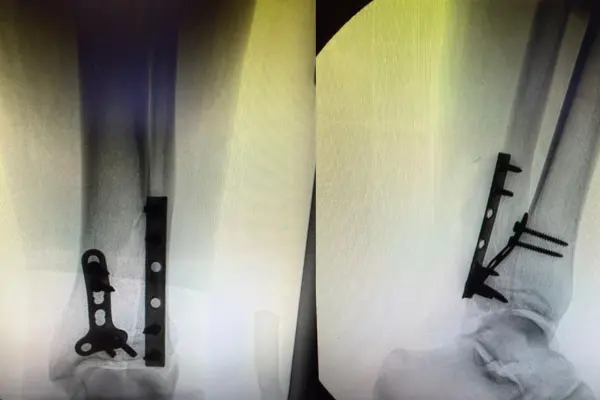

Execução da cirurgia com técnicas modernas e minimamente invasivas, utilizando implantes de última geração para fixação adequada da fratura.

Especialização: Cirurgia de fraturas de tornozelo, fixação com placas e parafusos, técnicas minimamente invasivas e reconstrução de lesões complexas do pé e tornozelo em Goiânia.